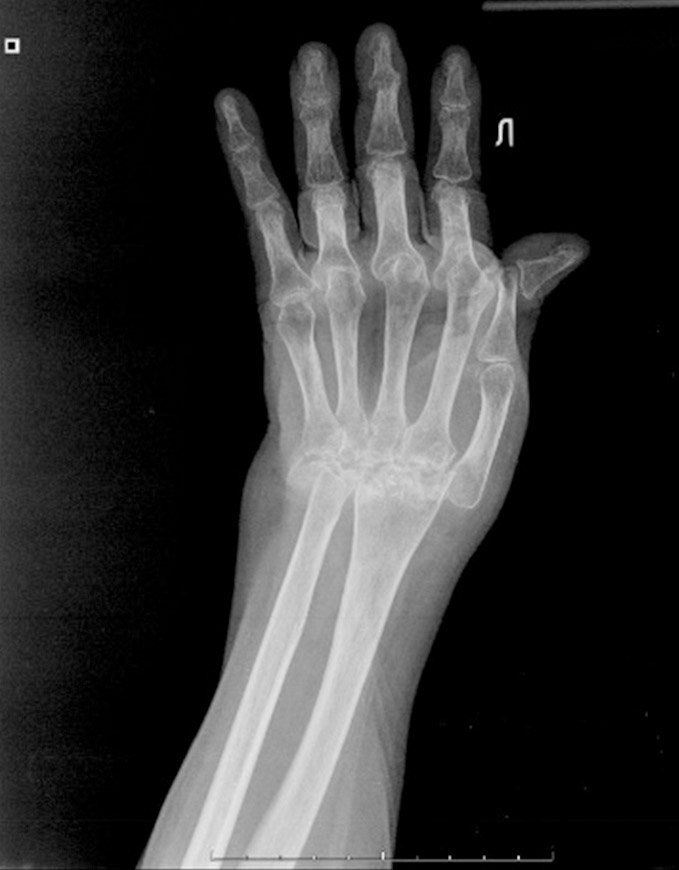

Рентгенологическая стадия поражения запястья определялась по классификации Larsen 1977 г. [12], которая в зависимости от степени сужения суставных щелей и выраженности костной деструкции включает пять стадий поражения суставов запястья. Согласно классификации Larsen, пациенты распределились следующим образом: у 8,7% была II стадия поражения суставов запястья, у 31,9% – III стадия, у 42,0% – IV стадия, у 17,4% – V стадия (рисунки 1–3).

Рисунок 3. Рентгенологическая картина тяжелого поражения суставов кисти с полным лизисом костей запястья.

Figure 3. X-ray pattern of severe stages of wrist deformities (Larsen V stage) with complete carpal bones osteolysis.